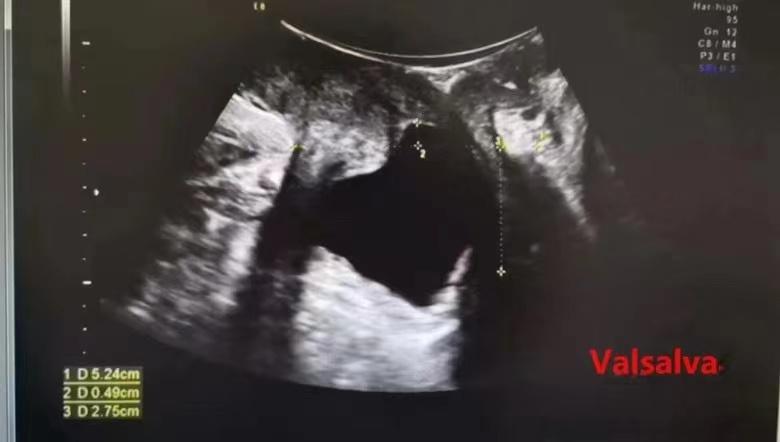

首先经阴道检查前、中、后盆腔,静息状态下与Valsalva动作下对比是否有膀胱、子宫、直肠脱垂及程度,缩肛运动观察肛提肌是否有损伤。